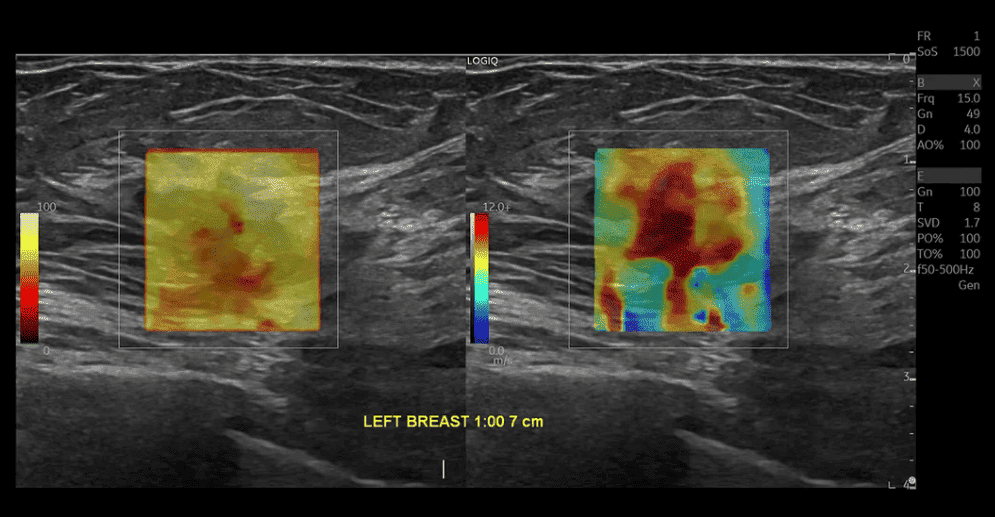

2D shear Wave Elastography로  조직의 탄성도를 수치화 하여 볼 수 있습니다. ‘단순히 딱딱해 보인다’가 아닌 객관적 데이터를 제공합니다. 추적 검사 시 변화 비교가 용이 합니다.  따라서 간경화 추적관찰, 갑상선과 유방에서 결절 위험도 평가에 보다 객관적 자료를 제공합니다